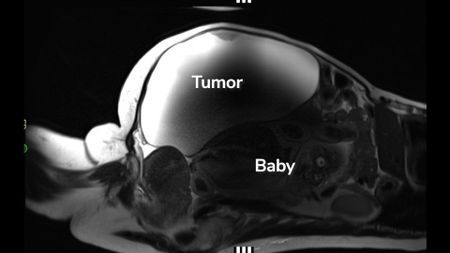

'Unprecedented': Woman delivers full-term abdominal pregnancy while also having 22-pound cyst removed